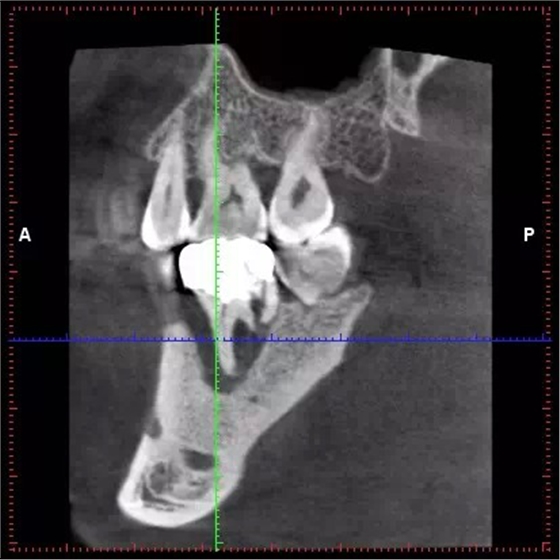

CBCT診斷牙周病變結(jié)果可靠

QQ圖片20150711104326.png

土耳其一項研究顯示,體素值0.150 mm3被認定為診斷牙周病變的臨界值;在牙周病變的診斷中,錐形束CT(CBCT)可被考慮為最可靠的影像學(xué)檢查模式。該論文4月22日在線發(fā)表于《口腔頜面放射學(xué)》(Dentomaxillofac Radiol)雜志。

該研究使用了12副帶有上下頜骨的顱骨。研究者使用銼刀分別在前牙、前磨牙和磨牙部位仿造牙周病變(骨開裂、竇道、骨開窗)。在本研究中,共有14例骨開裂、13例骨開窗、8例竇道患牙以及16例無牙周病變牙作為對照組。研究者使用兩臺不同機型的CBCT,獲得了在6種體素條件下(0.080、0.100、0.125、0.150、0.160、0.200 立方毫米體素值)的影像。使用Kappa系數(shù)評估在不同影像條件下的研究者組內(nèi)及組間一致性。

結(jié)果為,在0.080立方毫米體素值下的影像總體組內(nèi)Kappa值為0.978~0.973;0.160 立方毫米體素值下為0.751~0.737,該結(jié)果表明在診斷牙周病變上,上述兩種情況下具有較高的研究者組內(nèi)一致性。CBCT診斷骨開窗準確性要顯著優(yōu)于診斷竇道及骨開裂(P<0.05)。而骨開裂與竇道的診斷準確性相比則沒有顯著差異(P>0.05)。(馬若晗 編譯)